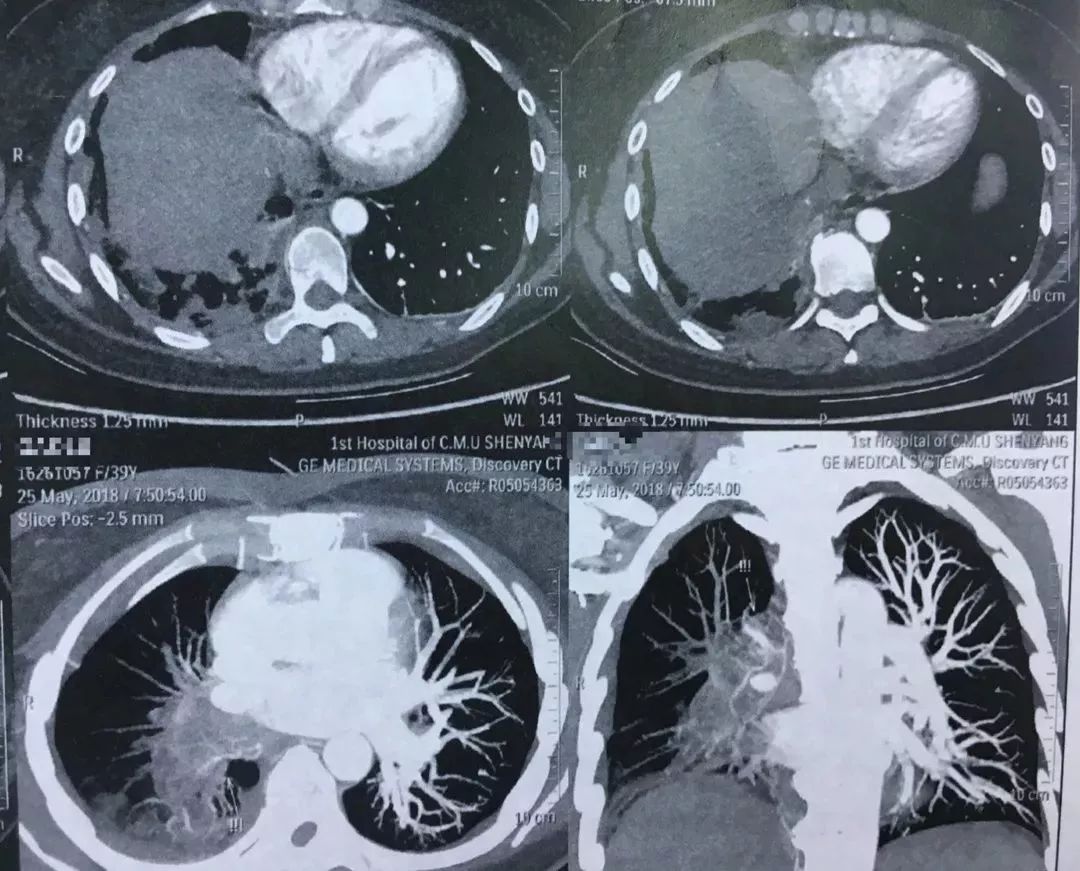

这样的充盈缺损是肺栓塞

图片尺寸1080x1049

图片尺寸1080x815